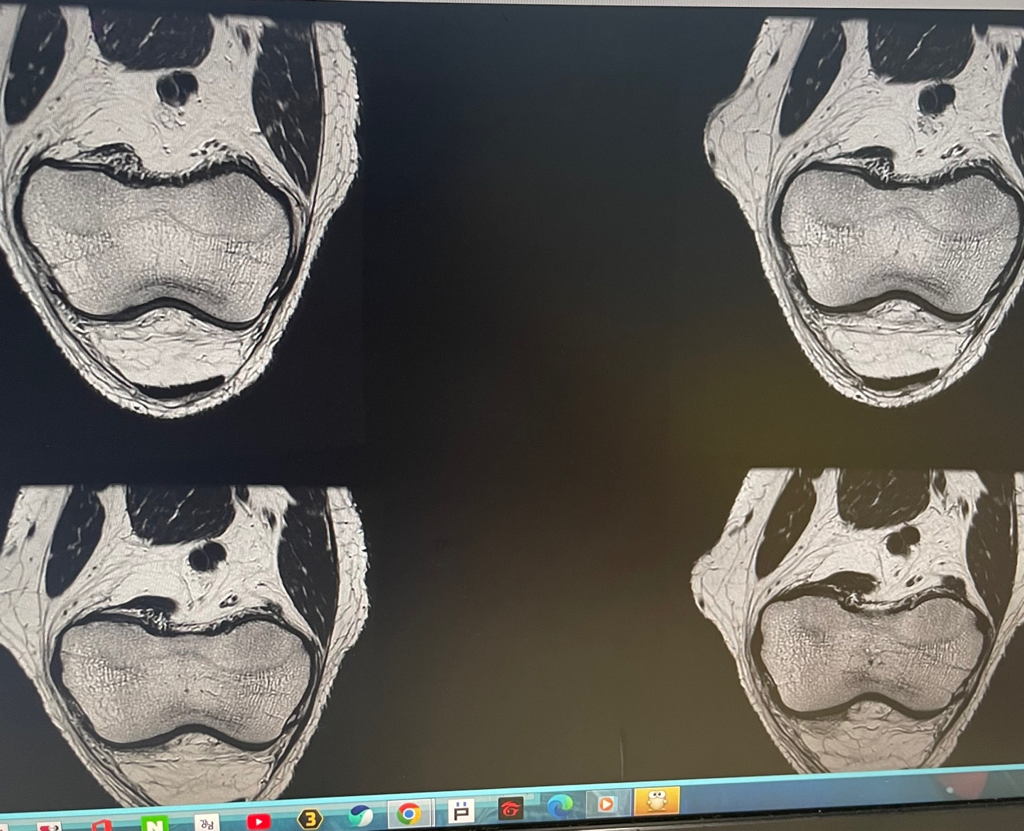

무릎 mri 원형원골인지 봐주실 수 있을까요

무릎이 너무 자주 아파서 mri를 찍어봤는데 무릎 연골에 이상이 있을까요

무릎이 선천적으로 원형연골인지 봐주시면 감사하겠습니다

MRI 판독에는 퇴행성 연골 손상, 바깥쪽 원판형 반월상 연골 이 의심된다고 적혀 있습니다.